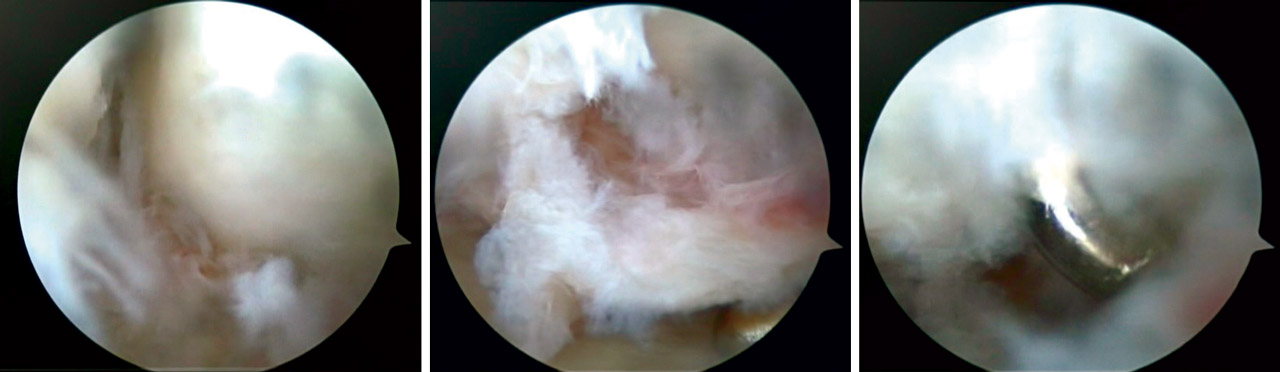

• En fracturas con componente principalmente articular se realiza artroscopia de inicio y la fijación de la fractura se efectúa visualizando directamente la reducción “fragmento a fragmento”, sosteniéndolos en empalizada con agujas de Kirschner (AK) o tornillos percutáneos, comprobando de forma directa la reducción de la superficie articular (Figura 5). No se realizó fijación con placa volar en estos casos.

El tratamiento de las lesiones asociadas fue realizado en función del grado y el tipo de lesión asociada (Figura 6), como se detalla a continuación.

• Grado III: RAFI con anclaje-reparación ligamentosa y fijación con tornillo a compresión escafosemilunar (Figura 7).

En roturas periféricas se realizaron suturas directas anclando el fibrocartílago a la cápsula articular. En las roturas foveales se procedió a la reinserción foveal con anclaje óseo mediante dispositivo PushLock® (Arthrex) (Figura 8). Ambas técnicas se realizaron de forma artroscópica.

En casos de lesión completa de grado III y IV realizamos desbridamiento artroscópico y fijación interna mediante tornillo percutáneo semilunopiramidal (Figura 9).